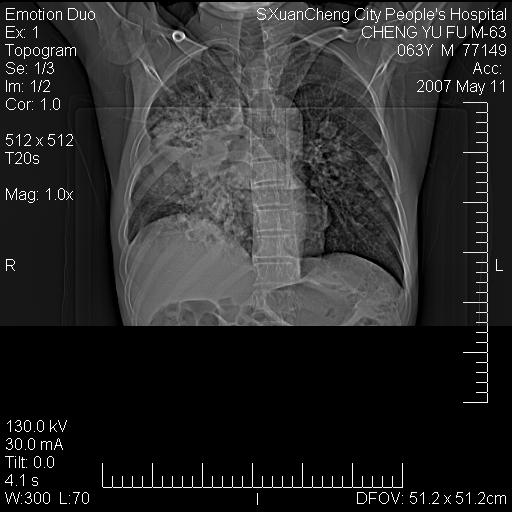

以下是引用小初学者在2007-5-11 19:32:00的发言:[br]1、首先考虑干酪性肺炎支气管播散[br]2、支气管肺泡癌待排

以下是引用zhangzhongshou在2007-5-11 19:30:00的发言:[br]细支气管肺泡癌可能性大。